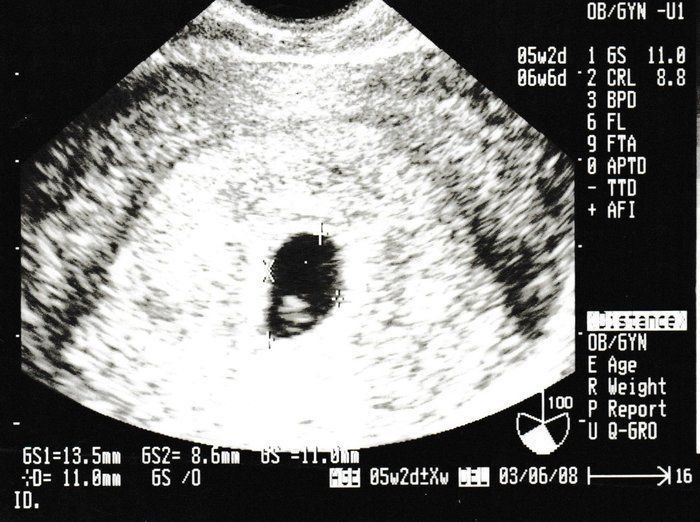

ちゃじゅびさんの妊娠6週目のエコー写真 胎芽が見える

胎嚢が大きくなり、そのなかに胎芽(7週未満の赤ちゃん)が確認できるようになりました。